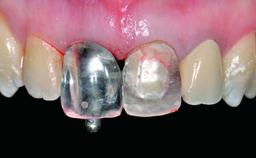

A healthy 38-year-old male patient was referred for replacement of a failing tooth-supported cantilever fixed dental prosthesis on teeth 11 and 21. The patient reported a history of trauma at 13 years of age that had resulted in the subsequent loss of tooth 11, as well as endodontic treatment of the adjacent abutment tooth 21. A metal-ceramic cantilever fixed dental prosthesis replacing tooth 11 had been provided by his general dentist several years after the loss of the tooth, with tooth 21 as the sole abutment. At the time of initial presentation, this restoration had been in service for over 20 years.